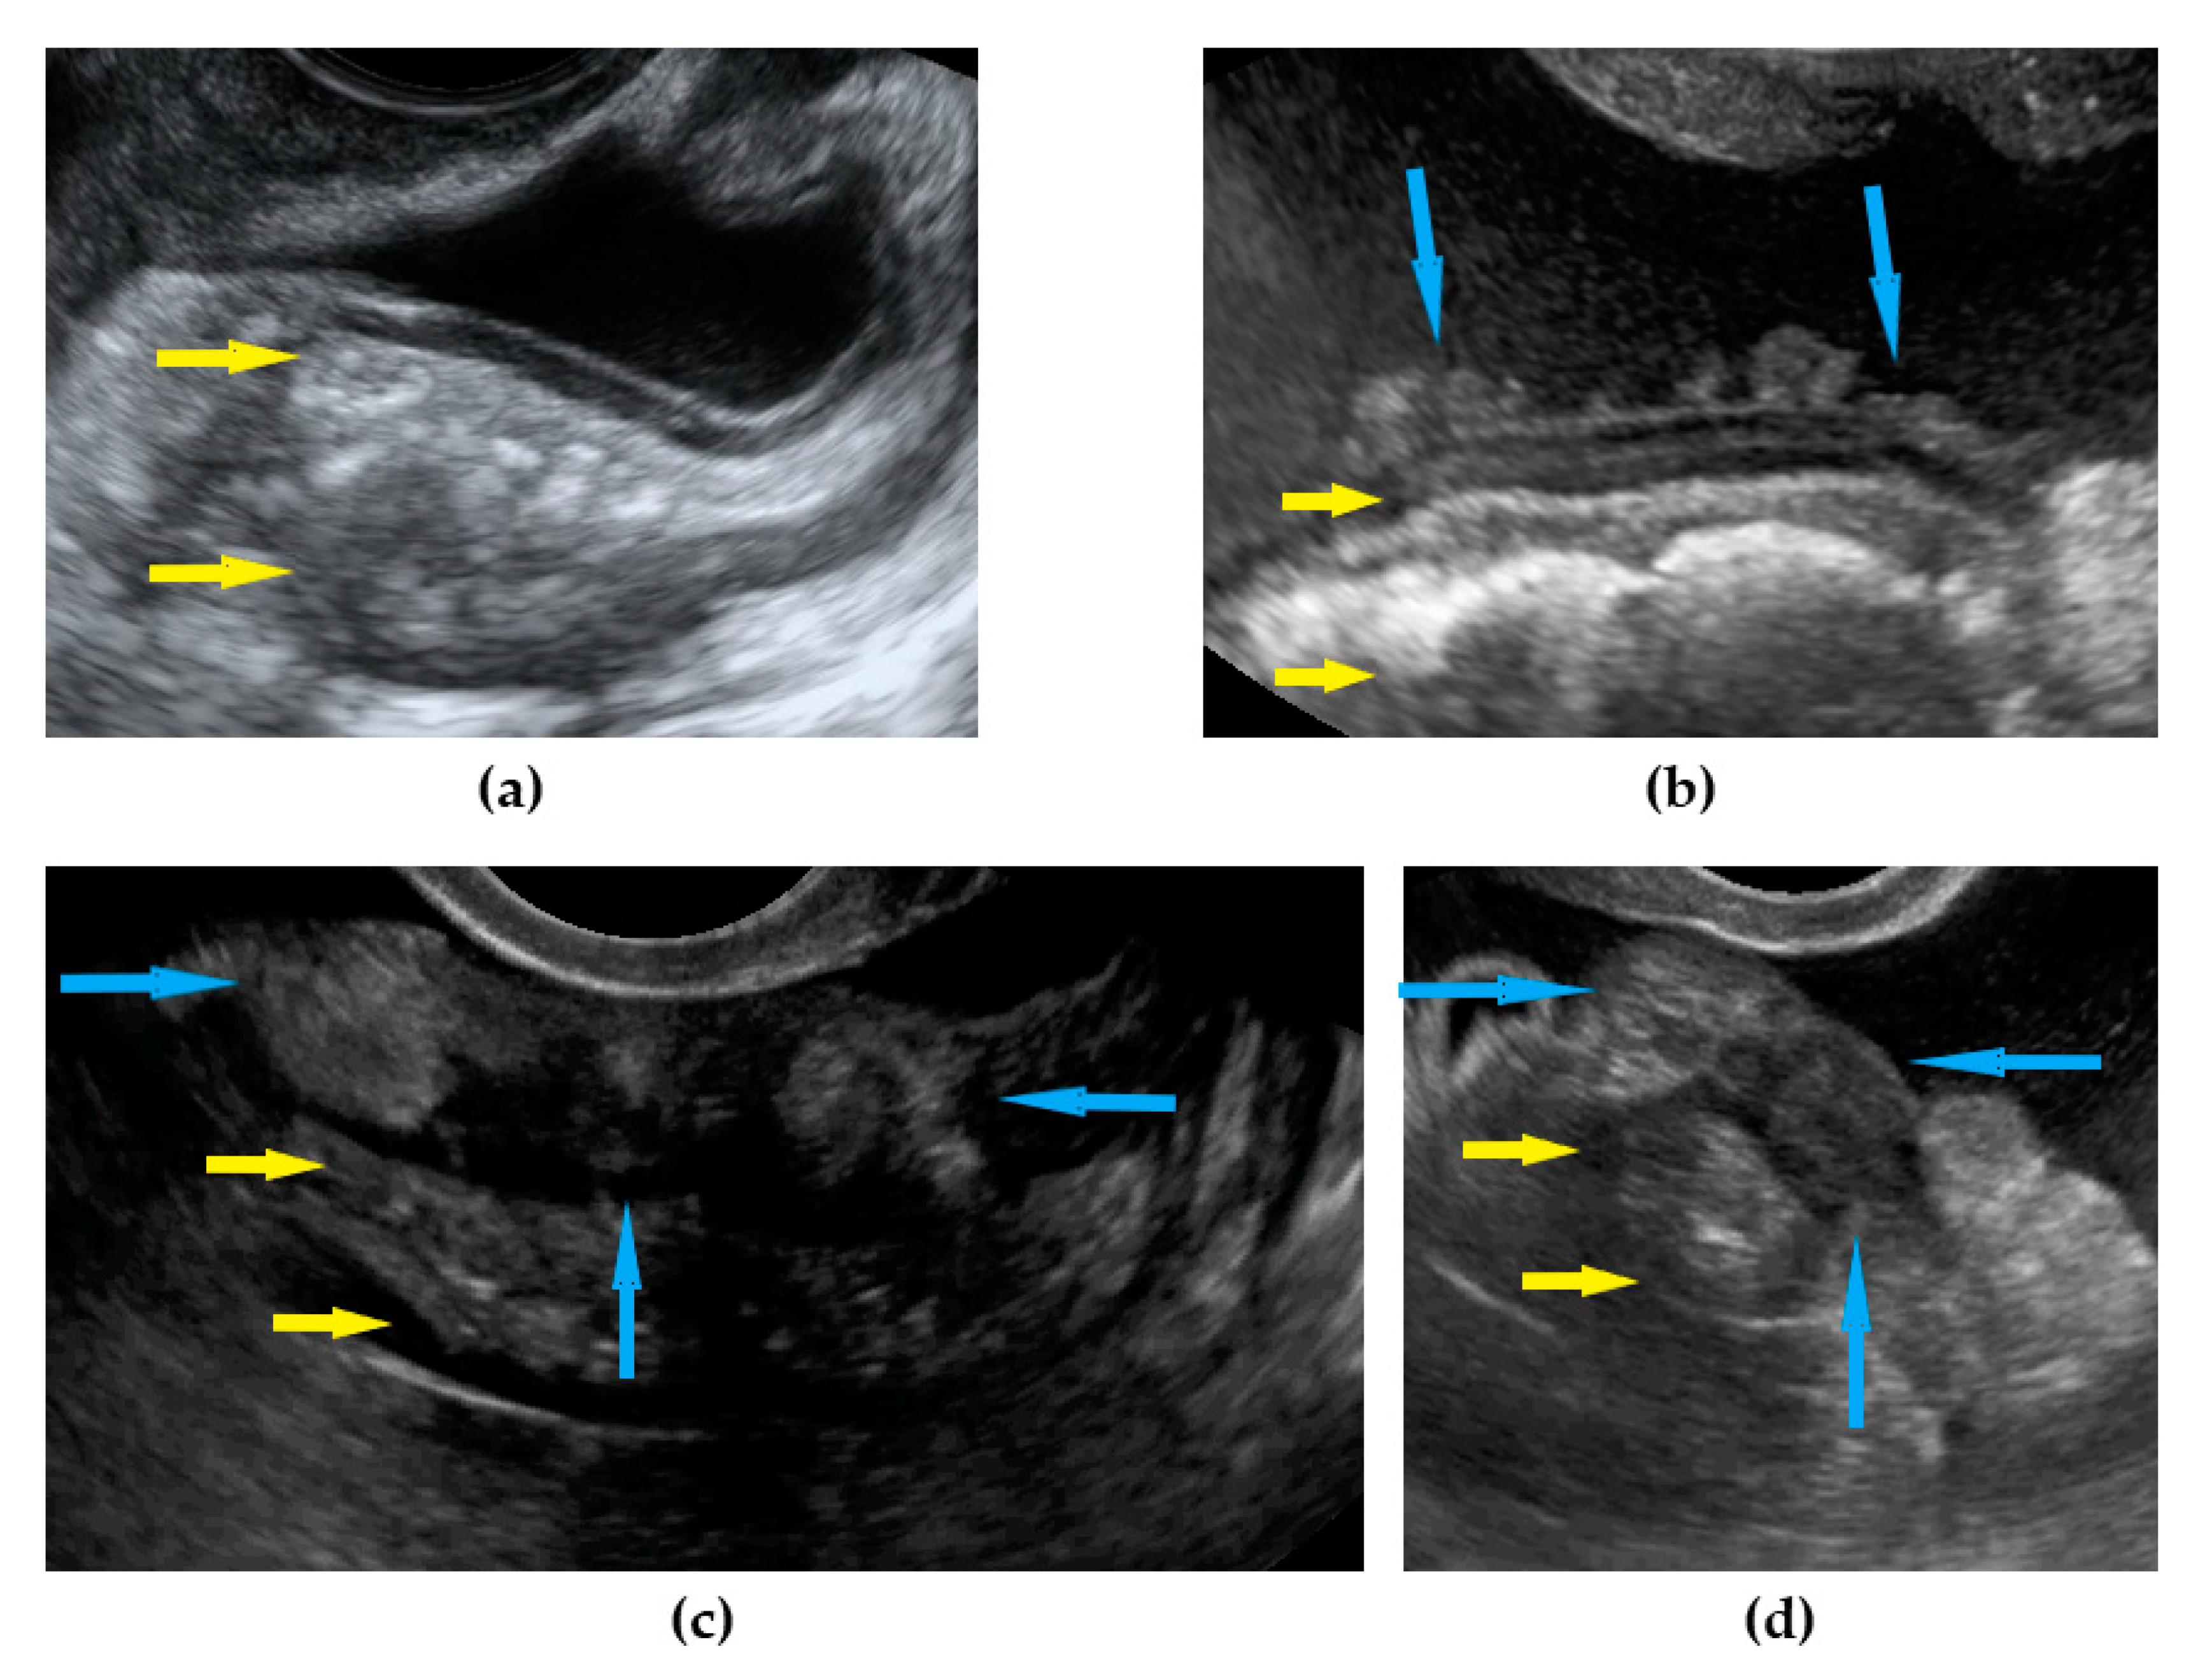

| Omentum | Focal infiltration of omentum: hypoechogenic nodules with discrete vascularization. Diffuse infiltration: omental cake appears as a nodular, perfuse, and non-peristaltic tumor that is located between the anterior abdominal wall and bowel loops. | Figure 1 | Video S1 |

| Small bowel mesentery root | Involvement is suspected when bowel loops have poor mobility and are “fixed together” in the dynamic ultrasound examination with a cauliflower-like image. | Figure 2 | Video S2 |

| Peritoneum, abdomen | Abdomen carcinomatosis manifest as hypoechogenic lesions over the peritoneal surface of the paracollic gutters or internal abdominal wall. | Figure 3 | Video S3 |

| Peritoneum, pelvis | Pelvic carcinomatosis manifests as hypoechogenic lesions over the peritoneal surface of the pelvic wall: laterally, in the pouch of Douglas (no rectum involvement) or the bladder in the uterine serosa. | Figure 4 | Video S4 |